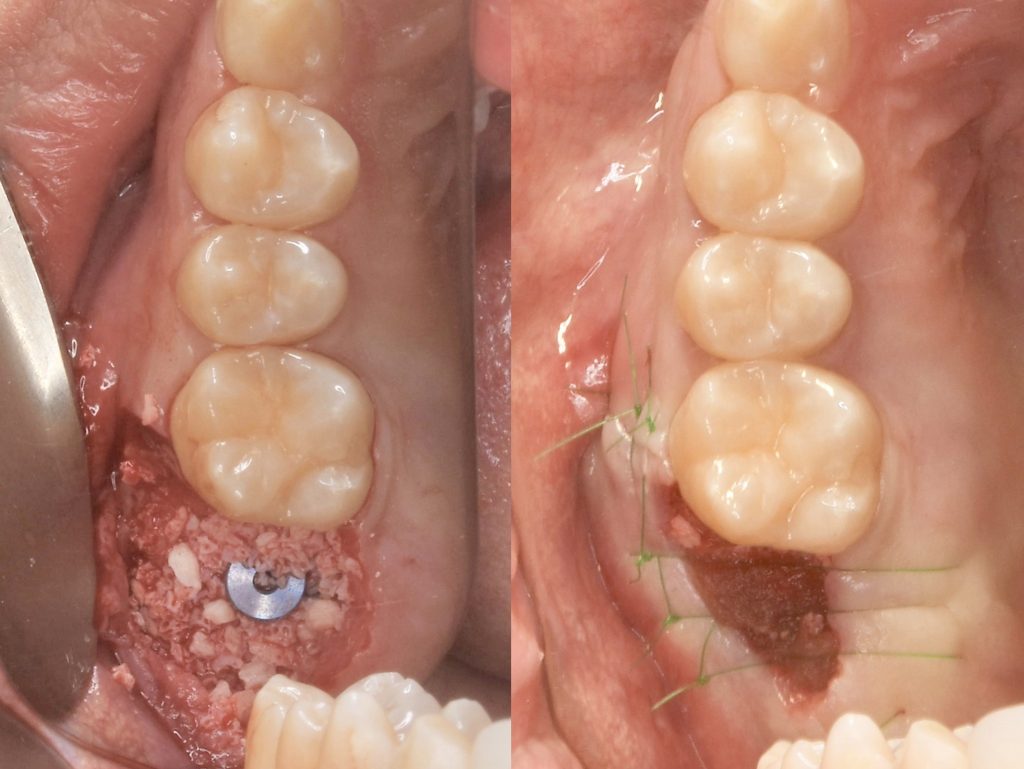

下記の症例は新しくローンチされるインプラントを前もって使用感を確認する為に、適したケースに使わせていただいております。

今回のケースは新しいインプラントを使うことで、骨造成の負担を減らし、清掃性を高める事ができました。